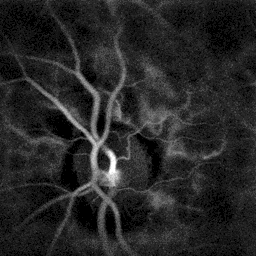

- Fluorescein angiography is a helpful adjunct. Findings include delayed venous filling, hypofluorescence caused by hemorrhage and capillary nonperfusion, dilation and tortuosity of veins, leakage due to neovascularization and macular edema.

- Laser Doppler imaging[3] reveals dynamic hemodynamics discrepancies between branch arteries and veins, from local vascular resistance increase by the venous occlusion.

Branch retinal vein occlusion revealed by laser Doppler imaging through flow alteration in the upper right branch artery.